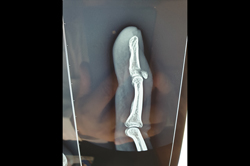

Finger Tip Injury - JESS

Finger Tip injury